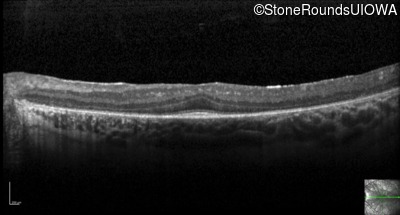

Optical Coherence Tomography - Right - 20/50

Exemplar / OCT Stack